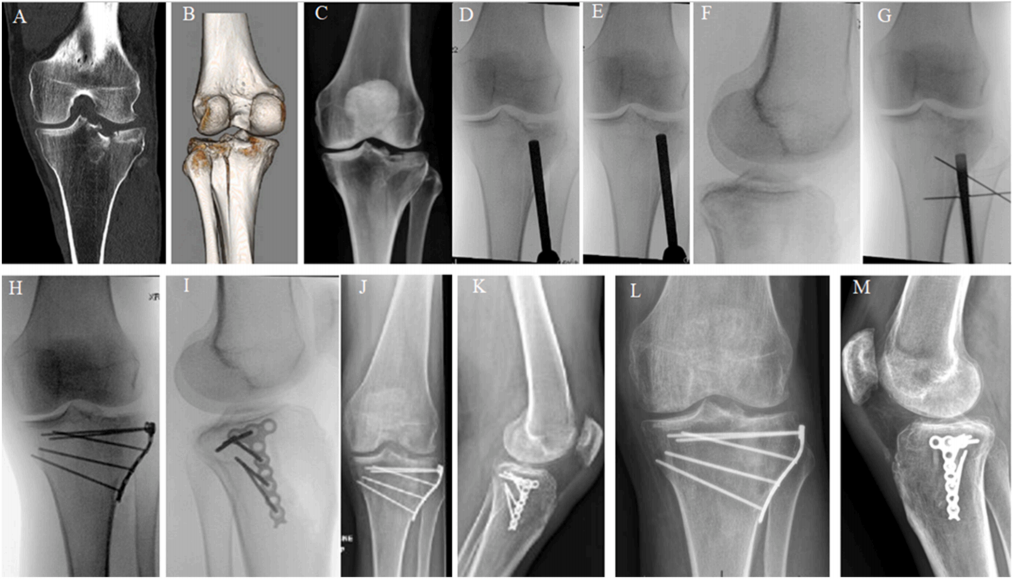

A-D) 55 岁男性多髁粉碎性胫骨平台骨折的 3D CT 图像。 E, F) 使用扩展后侧入路对后侧和内侧部分进行一期 ORIF 的术中 C 臂机图像。注意内侧边缘水平放置的钢板 G, H)。 I, J) 一期手术后 3 天,通过前外侧和内侧切口对前内侧和前外侧部分进行二期 ORIF 的术中 C 臂机图像。 I, J) 使用磷酸钙骨腻子(骨水泥)支撑前内侧缺损。二期 ORIF 术后即刻 X 光片。 K, L) 术后 34 周随访 X 光片显示骨折愈合且固定稳定性可接受。可注意到内侧胫骨平台轻度塌陷,但考虑到骨折特征,仍在可接受范围内。

A-D) 54 岁女性患者多髁平台骨折(包括前外侧、外侧、前内侧和后内侧骨折)的 3D CT 扫描。 E-J) 术中 C 臂机 X 光片显示复位和固定的顺序。 J, K) 术后 24 周随访 X 光片显示骨折愈合且固定稳定。